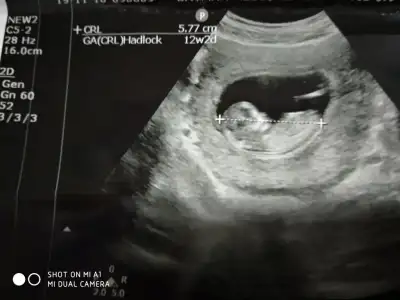

dr soylemeden siz gorun genital nub teorisi ( bebegin cinsiyeti)

Kızlar yorum istiyorum doktor daha küçük dedi 12 haftada ☺️☺️